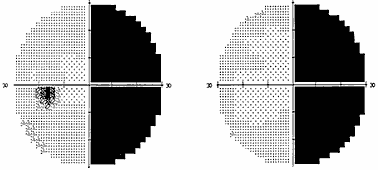

Рис. 1. Полная битемпоральная гемианопсия (автоматическая статическая периметрия) При наиболее часто встречающемся срединном варианте расположения хиазмы опухоль начинает сдавливать центральные перекрещенные волокна нижней поверхности хиазмы, идущие от носовых половин сетчатки. Клинически это проявляется появлением дефектов в верхних височных квадрантах поля зрения на обоих глазах – начальный хиазмальный синдром. Следует отметить, что дефекты в поле зрения поначалу можно выявить только с помощью цветных объектов, красного и зеленого. Исследование поля зрения на цвета более чувствительно, чем кинетическая периметрия на белый цвет. Острота зрения на этом этапе развития заболевания, как правило, сохраняется нормальной. Диски зрительных нервов обычной окраски. Постепенно, по мере роста опухоли, усугубляются битемпоральные дефекты поля зрения, начальный хиазмальный синдром переходит в развернутый хиазмальный синдром с полным или почти полным выпадением височных половин поля зрения. Появляется побледнение дисков зрительных нервов преимущественно в височной половине – развивается первичная нисходящая атрофия зрительных нервов. Важно знать, что изменения на глазном дне наступают спустя месяцы от момента развития первых дефектов поля зрения. Нередко, к сожалению, пациенты не фиксируют внимания на периферических дефектах в поле зрения и обращаются к офтальмологу только тогда, когда появляется понижение остроты зрения. Справедливости ради следует сказать, что порой и врачи не придают должного значения жалобам пациентов в случае сохранной остроты зрения и/или нормального диска зрительного нерва. Пациенты годами наблюдаются и лечатся у офтальмологов по поводу атрофии зрительного нерва. Понижение остроты зрения имеет место при воздействии опухоли на интракраниальный отрезок зрительных нервов, когда в процесс вовлекается папилло–макулярный пучок. Это происходит либо при непосредственном сдавлении зрительного нерва опухолью, либо в результате смещения его опухолью и придавливания нерва к серповидной связке или костным структурам интракраниального отверстия зрительного канала. Клинически симптом воздействия на интракраниальный отрезок зрительного нерва проявляется центральной или парацентральной скотомой. Но чаще это сочетается с периферическими височными дефектами поля зрения. Понижение остроты зрения возможно и в результате распространения височного дефекта поля зрения на центральную зону. Понижение остроты зрения может быть на одном или на обоих глазах. Сочетание понижения остроты зрения на одном глазу или на обоих, но разной степени выраженности, и битемпоральных дефектов поля зрения приводит к развитию асимметричного хиазмального синдрома, свидетельствующего об асимметричном росте опухоли. Понижение остроты зрения, которое появляется прежде или в относительно короткий срок после развития битемпоральных дефектов поля зрения, указывает на преимущественный рост опухоли кпереди – супраселлярно–антеселлярно или о заднем расположении хиазмы. При таком расположении хиазмы опухоль локализуется перед хиазмой, воздействуя в первую очередь или преимущественно на интракраниальные отрезки зрительных нервов. Внимание пациента также могут привлекать парацентральные битемпоральные скотомы. Острота зрения при этом бывает высокой. Наличие таких дефектов поля зрения свидетельствует о сдавлении задне–верхних отделов хиазмы, вблизи расположения папилло–макулярного пучка. Подобная симптоматика имеет место при росте опухоли интраселлярно и преимущественно кзади – супраселлярно–ретрохиазмально или при переднем расположении хиазмы. Характерной первой жалобой пациентов при таком варианте роста опухоли может быть жалоба на затруднение при чтении. Следует, однако, оговорить, что такой тип зрительных расстройств при аденоме гипофиза встречается достаточно редко. В силу различных причин, в частности, из–за строения диафрагмы турецкого седла, опухоль может распространяться не столько кверху, сколько латерально, в сторону кавернозного синуса – латероселлярный рост. Зрительные нарушения, которые присутствуют при этом росте опухоли, чаще представлены асимметричным хиазмальным синдромом со значительным, вплоть до практической слепоты, понижением остроты зрения на одном глазу. Может также развиться одноименная (односторонняя) гомонимная гемианопсия (рис. 2) в результате воздействия опухоли на зрительный тракт. Дефекты поля зрения появляются в половине поля зрения на стороне, противоположной локализации опухоли. Офтальмологи должны быть внимательны, поскольку дефекты поля зрения при латероселлярном росте опухоли и развитии асимметричного хиазмального синдрома или гомонимной трактусной гемианопсии появляются в носовой половине поля зрения на глазу на стороне преимущественного роста опухоли (рис. 3). Это может спровоцировать ошибочную диагностику глаукомы.

Рис. 2. Полная правосторонняя гомонимная гемианопсия (автоматическая статическая периметрия)